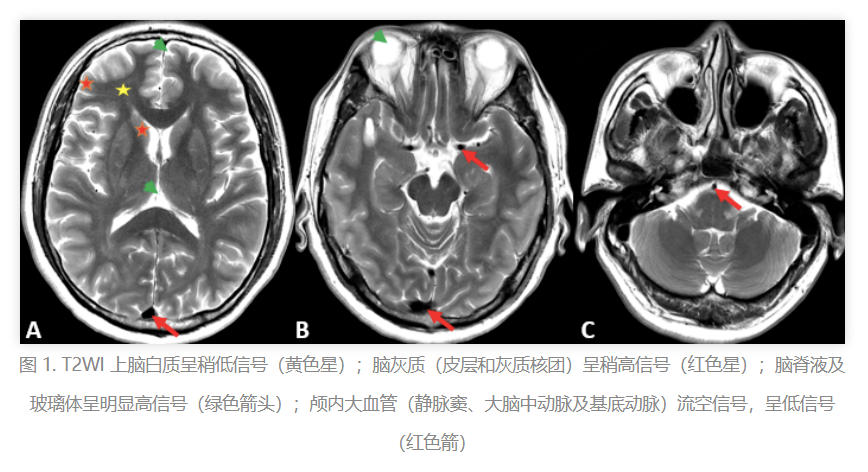

T2WI:看大脑的病灶,就像是给大脑拍了一张“夜景照”,病灶在黑暗中更显眼。

T2WI:脑灰质亮,脑白质暗,像是一张夜晚的星空照。